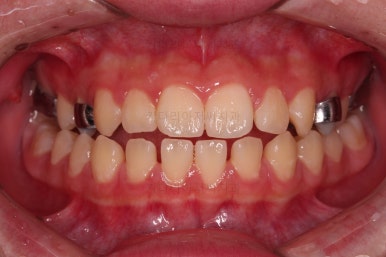

틈이 다 모였고 교합도 많이 좋아졌죠?

끝내도 될까요?

전후 사진을 비교해 볼게요.

악궁확장을 통해 위아래 악궁의 크기 조화를 맞췄고, 틈새도 모았으며 교합도 적절히 마무리를 했습니다.

웃는 모습도 훨씬 예뻐졌네요.